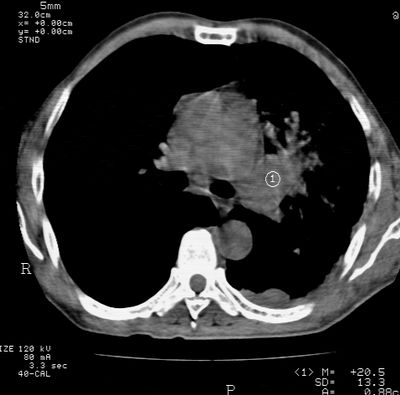

标题: CT24000:M65,胸痛,胸闷月余,既往慢支,肺气肿,肺心病 [打印本页]

标题: CT24000:M65,胸痛,胸闷月余,既往慢支,肺气肿,肺心病

左肺门肿块,相应支气管闭塞,左肺上叶、舌叶大片及散在高密度影,部分呈不张改变,两肺纹粗乱,左侧胸腔积液。考虑左侧中央型肺癌伴阻塞性改变。

左肺门见巨大软组织肿块影,直径约--,境界清,左上肺叶支气管变窄,左上肺舌叶见大片状密实影,余肺纹理增多、紊乱、纤细、部分网格状,两肺透亮度增高,纵隔内见增大多发淋巴结影,心影略左偏,左侧少量胸腔积液。

左侧中央型肺癌伴左上肺舌叶不张、纵隔淋巴结转移,左侧少量胸腔积液。